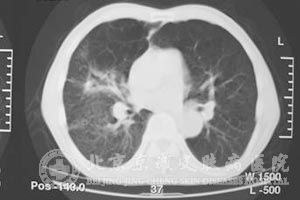

肺鳞状*癌的晚期患者治疗上就非常困难了,那么晚期肺鳞癌患者应注意什么才能延长生命呢?

北京京城皮肤医院指出,如何延长癌症患者的寿命,这是人们一直在研究探讨的问题,也是人们非常关注的问题。一般说来,注意日常的生活习惯,保持健康乐观的心态,积配合治疗,可有助于晚期的肺鳞状*癌患者延长生命。